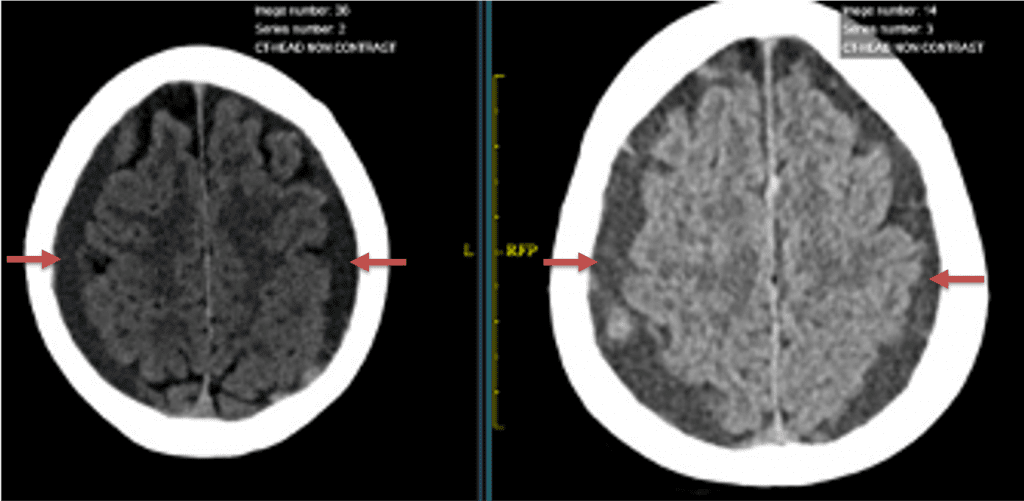

CT follow-up at 1 week demonstrates early resorption. 2 weeks post MMA embolization, resolution of the left subdural collection with new small thin acute hemorrhage in an otherwise stable right subdural collection is observed (Figure 3. A and B).

Figure 3. A) 1 week post MMA embolization demonstrating decreasing thickness bilaterally B) 2 weeks post MMA demonstrates resolution on left, with small new acute component on right with overall decreased thickness.